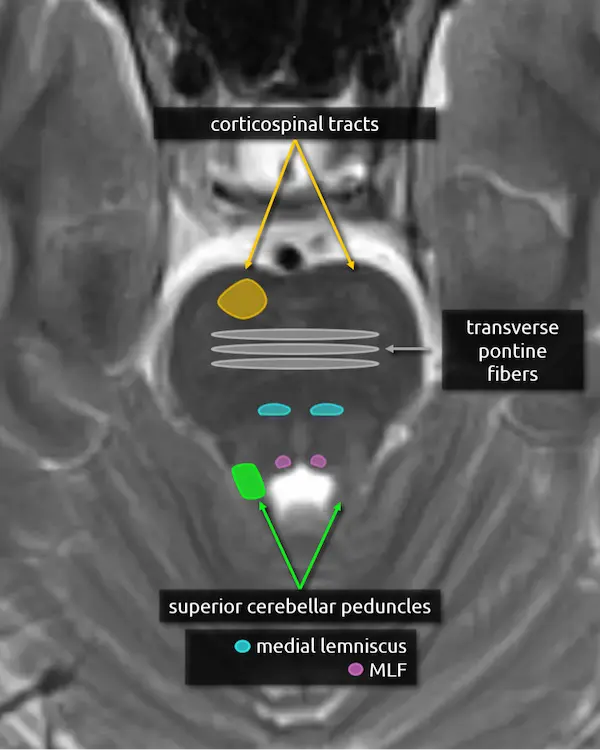

1. Corticospinal tracts

2. Superior cerebellar peduncles

3. Middle cerebellar peduncles:

The middle cerebellar peduncles are the largest of the cerebellar peduncles and connect the cerebellum to the pons. The fibers are entirely afferent, originating from contralateral pontine nuclei and terminating in the cerebellum. Over 90% of the fibers in the middle cerebellar peduncles belong to the corticopontocerebellar pathway (see below).

There are many causes of middle cerebellar peduncle signal abnormality, usually resulting from conditions that can cause white matter edema, degeneration, or gliosis. Bilateral T2 hyperintensity of the middle cerebellar peduncles is a classic but not specific sign of fragile X-associated tremor/ataxia syndrome (FXTAS). Multiple system atrophy cerebellar type (MSA-C) and spinocerebellar ataxia are other classic causes of middle cerebellar peduncle atrophy and signal abnormalities.

4. Transverse pontine fibers:

The transverse pontine fibers form the bulk of the mid pons and are crossing white matter tracts that go to, or come from, the cerebellum via the middle cerebellar peduncles. The majority of the fibers belong to the corticopontocerebellar pathway, which is crucial for motor coordination and learning.

A lesion that involves the transverse pontine fibers is likely to produce ataxia.

2. Middle cerebellar peduncles

3. Middle cerebellar peduncles

4. Transverse pontine fibers

5. Medial lemniscus

6. Medial longitudinal fasciculus (MLF)